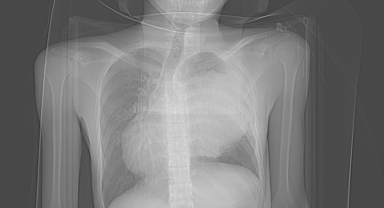

Endonezyalı turist tatil için geldiği Alanya'da göğsündeki 3 kiloluk kitleden kurtuldu 06 Eylül 2022 - 11:40